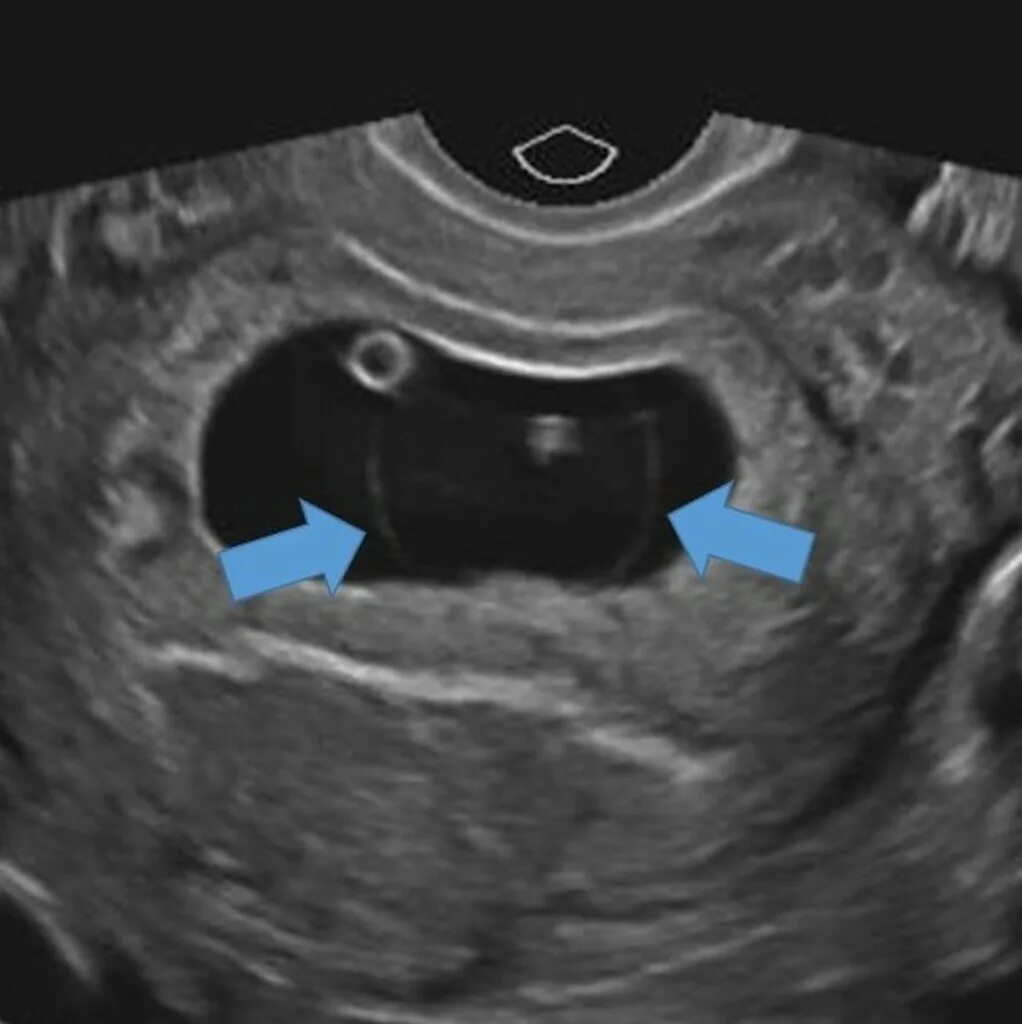

Желточный мешок 2 мм